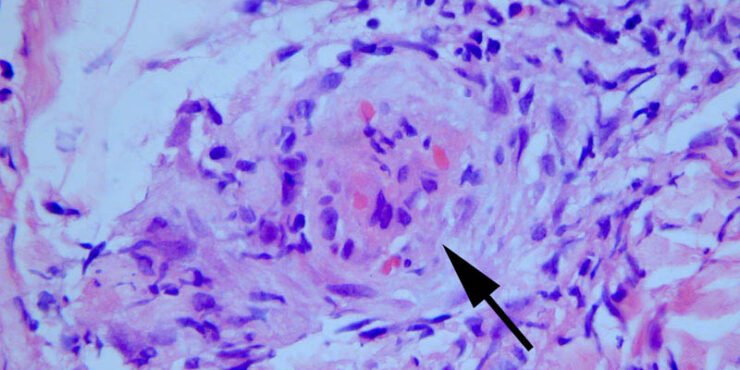

Suture granuloma = الحبيبوم مكان الغرزة الجراحية